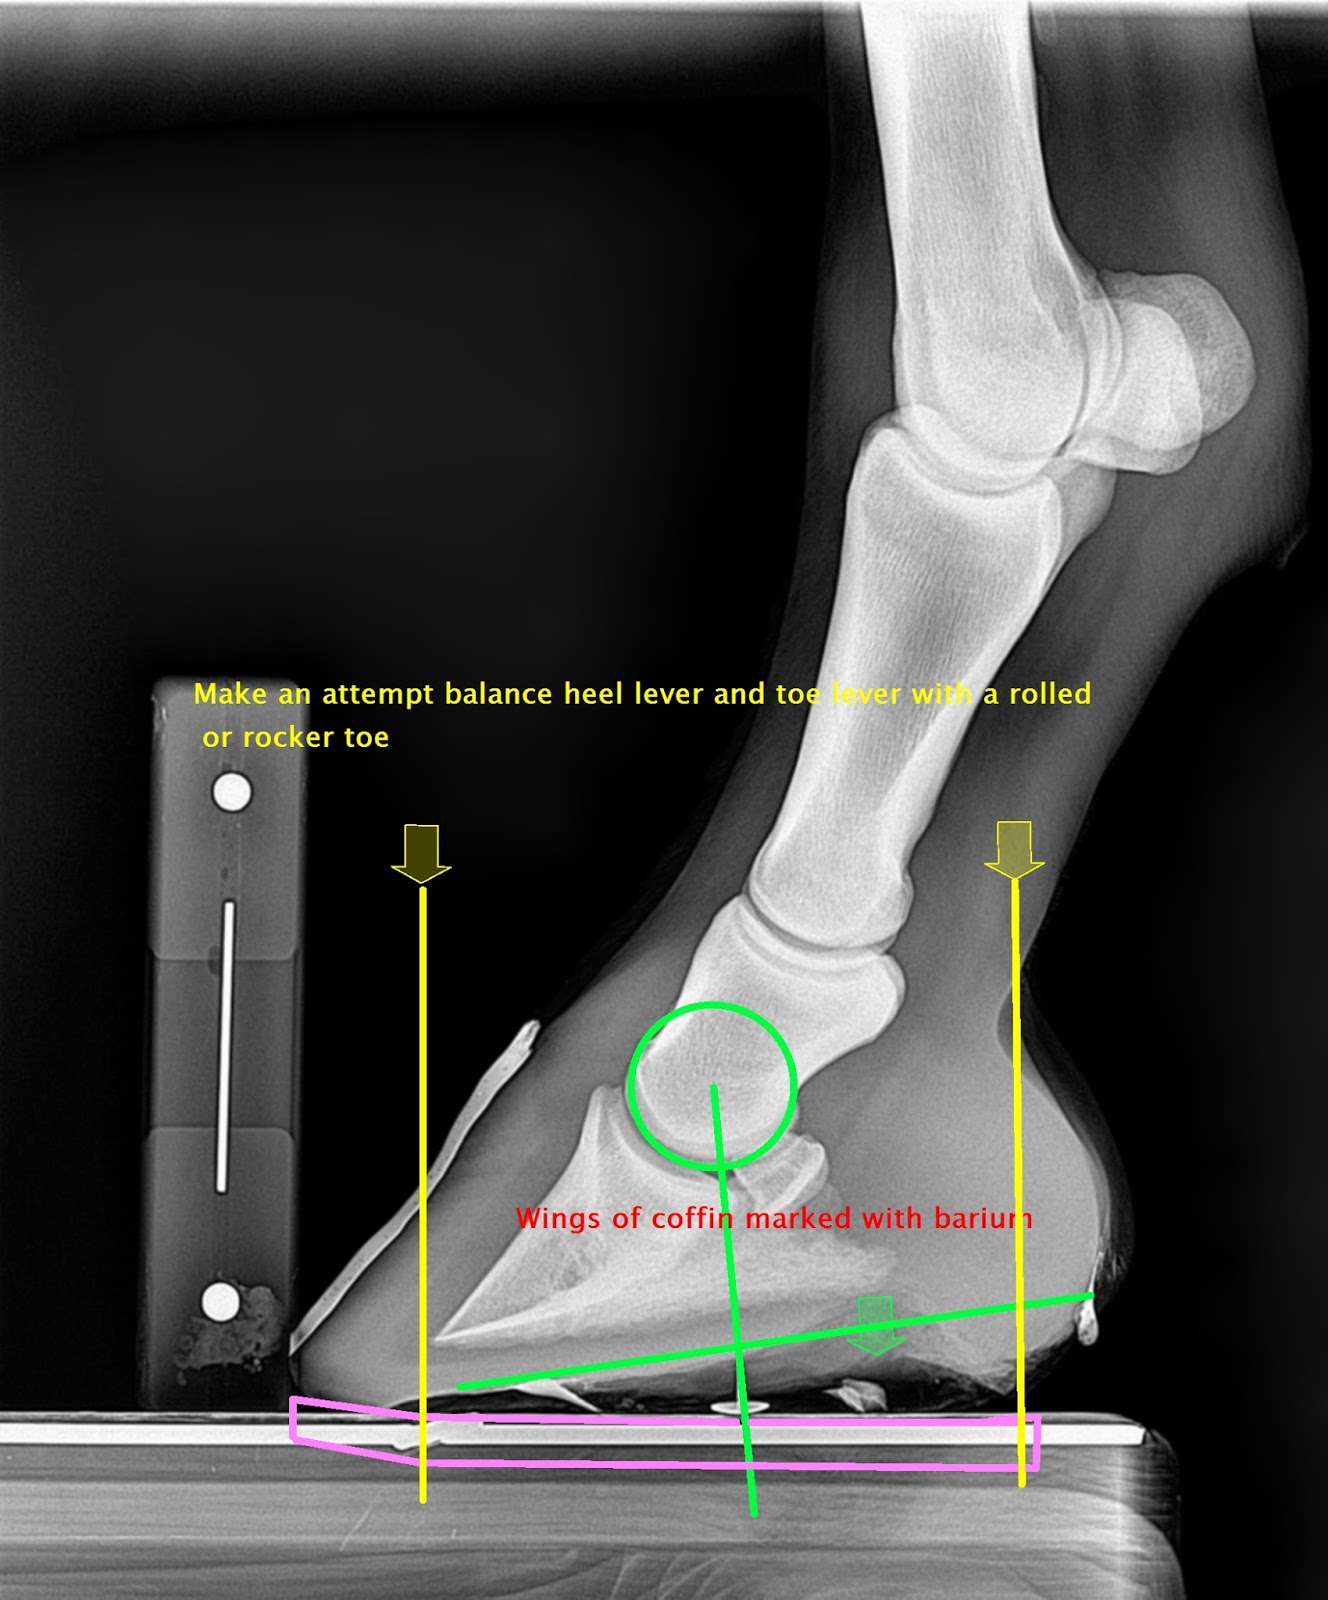

Note the centre if rotation is drawn perpendicular to the bearing surface of the hoof and not the shoe

A palmar shift in the orientation of CoP as a result of increased elevation is compensated for by an increase palmar bearing border length and rolled toe mechanics